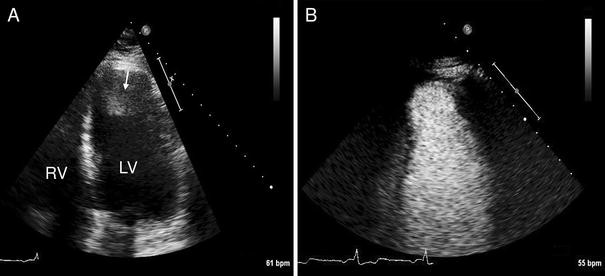

Assessment of an intracardiac thrombus using CEUS. A 61-year old man with a history of a large apical-anterior myocardial infarction was referred for echocardiography for the evaluation of cardiac thrombus. a Standard echocardiography (apical 4 chamber view) demonstrates an abnormality in the left ventricular apex which was a suspected thrombus (arrow). b CEUS demonstrates that there is actually no thrombus in the left ventricular apex. The abnormality that was observed on standard echocardiography was probably a reverberation artefact

The evaluation of cardiac thrombus by CEUS may have a direct impact on the management of the patient, and may lead to changes in medical therapy (anticoagulation). Additionally the detection of an intracardiac thrombus by CEUS may prevent defibrillation threshold testing in patients with an implantable cardioverter defibrillator (ICD).